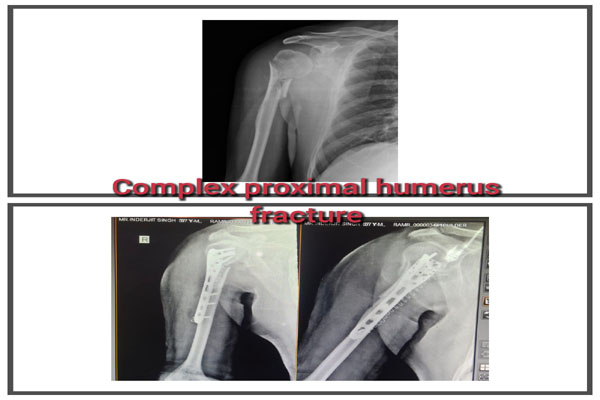

Fracture of bones is commonly handled by almost all orthopaedic surgeons in India. But dealing with comminuted intra-articular fractures (involving joints) is a night mare for most of them. It requires special expertise and experience to deal with such kind fractures. It can involve pelvic acetabular fracture, upper portion of thigh bone ( hip), lower portion of thigh bone ( femur), upper portion of arm bone (humerus head), lower portion of arm bone (humerus), lower portion of forarm bone (lower end of radius) fracture of heel bone, etc. The idea is to maintain the joint (articular) integrity and prevent the permanent loss of movements at that joint. It requires image intensifier (c-arm) to do these surgeries. May be artificial bone or autograft (patient’s own bone taken from iliac bone) to fill in the bone defect/ loss if present. The fracture may take 2- 3 months to heal. Patient may require prolonged physiotherapy to gain near normal range of motion exercises.